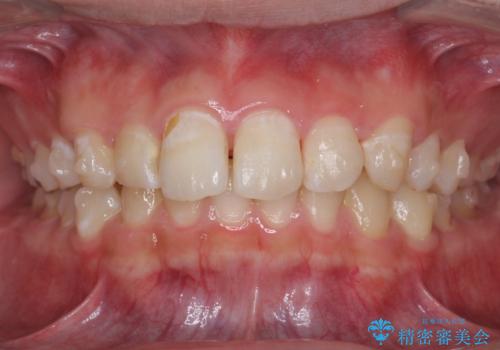

出っ歯が気になる 歯をぬかずに治療

- 前歯が出ているのを気にして来院。

左のかみ合わせが1本分ずれていましたが、機能的には問題ないのでそのまま変えずに治療しています。

右のかみ合わせをそのままに、最小限の動かし方で見た目を改善しました。